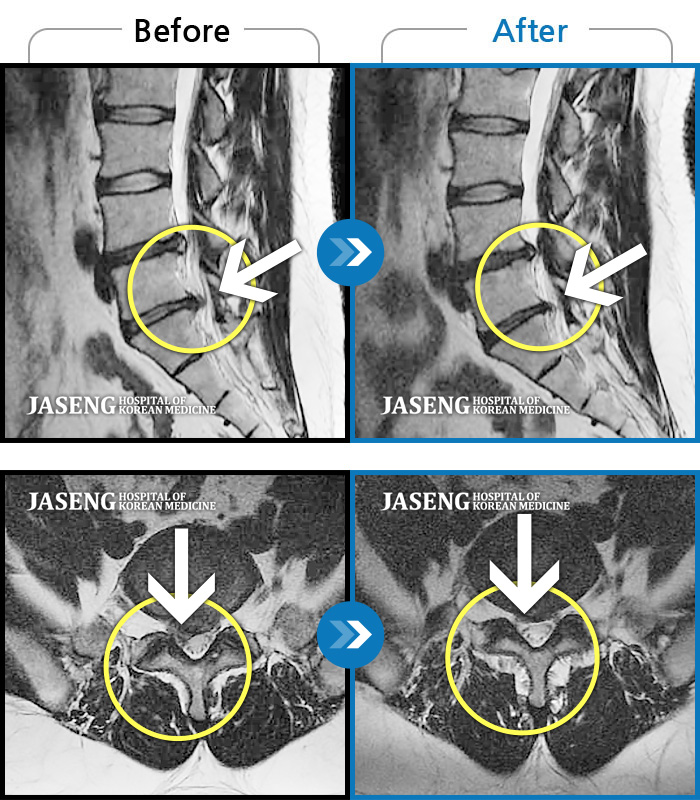

허리디스크

잠실 · 한상욱 원장

허리통증과 함께 좌측 엉치, 허벅지, 종아리 후면으로 저림이 심하여 걷기가 힘들어요.

촬영시기

2021.09.14 ~ 2022.05.14

2022.05.24